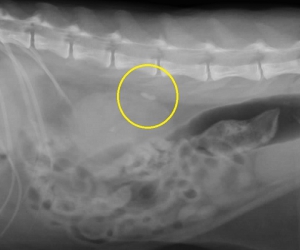

下のレントゲン像の黄色の縁で囲んだ目立たない結石は画像でこそ目立ちませんが、急性の尿管閉塞を生じている尿管結石です。尿管閉塞というのはお腹の中で腎臓から膀胱をつなぐ細い尿管で生じます。尿路閉塞として一般的な膀胱結石による尿道閉塞とその仕組みは同じです。

尿道結石は尿道という体の外に出る管での問題ですから、体外から結石除去を試みることができます。ところが尿管閉塞はお腹の中ですから手術以外の方法で結石に到達することができません。内科的に結石を尿管から膀胱へ落とすためには利尿薬などを組み合わせた点滴療法で自然排泄を図りますが、単独では決して確実な方法ではありません。